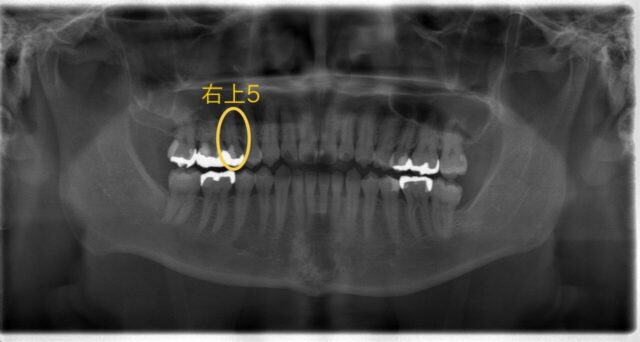

まずはパノラマ写真と口腔内写真をご覧下さい。

今回の部位は右上5番です

元々は金属の詰め物が入っていました。